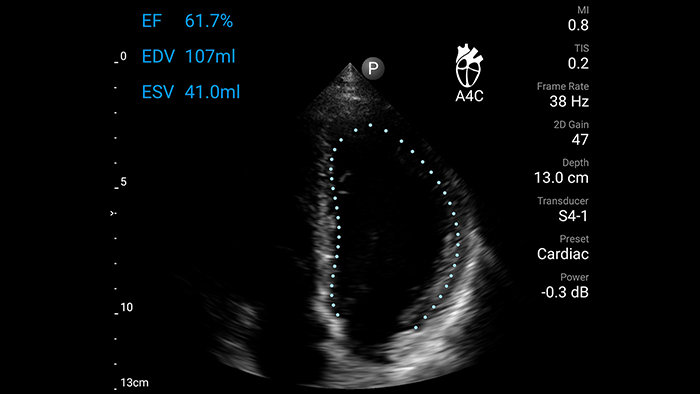

Now with AI-powered Auto EF for cardiac scanning[1]

Calculate ejection fraction (EF) using a single 4-chamber apical view of the heart without manual editing. Auto EF is designed to standardize quantification and reduce subjectivity among users of varying ultrasound experience.